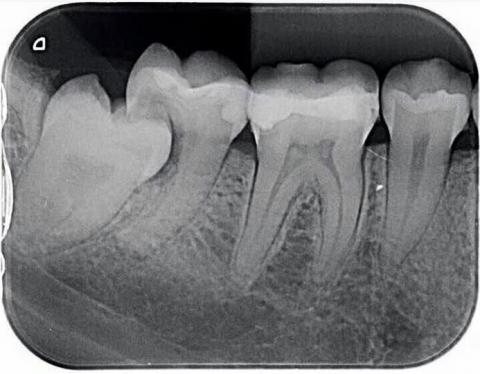

Upon examining the dental X-ray, it shows a partially erupted third molar (wisdom tooth) that is horizontally impacted against the adjacent second molar. This type of impaction is known to cause several complications if left untreated.

The close proximity and pressure from the impacted wisdom tooth may lead to food impaction, gum inflammation, interproximal caries, root resorption, and even infection spreading to surrounding tissues. The area also appears prone to bacterial accumulation due to limited cleaning access, which can result in bad breath, gum bleeding, and localized pain.

Horizontally impacted third molar (wisdom tooth)

Early carious lesion risk on the distal aspect of the adjacent molar

Potential pericoronitis or localized periodontal inflammation